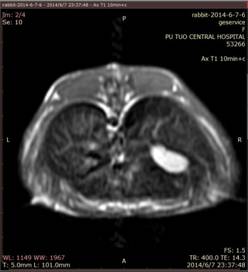

2、肝脏肿瘤造影